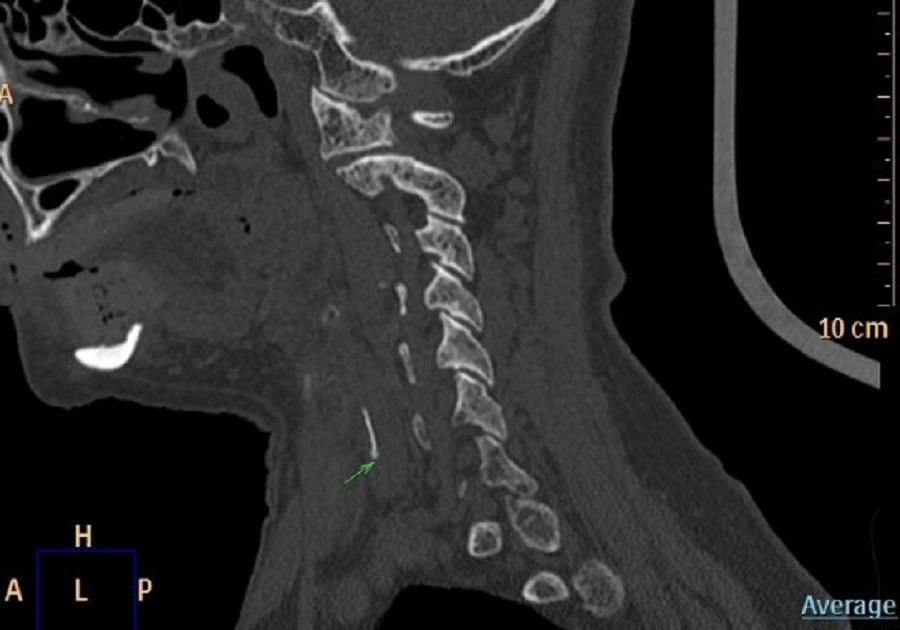

Sau khi được đưa đến phòng khám, nội soi Tai Mũi Họng phát hiện phù nề nghiêm trọng ở vùng sụn phễu trái. X‑quang cổ nghi ngờ có dị vật và CT xác định một mảnh xương cá kích thước khoảng 1×22 mm đã xuyên ra khỏi ống tiêu hoá, cắm sâu vào thùy trái tuyến giáp.